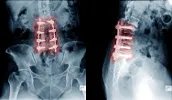

The surgery requires bone grafting to form a bridge between the affected vertebrae, with placement of screws, plates and rods into healthy bone to hold it all together. The result, depending on the number of levels (number of vertebrae affected) is a spine that no longer moves naturally, with healthy bone that is overly stressed and may become compromised.